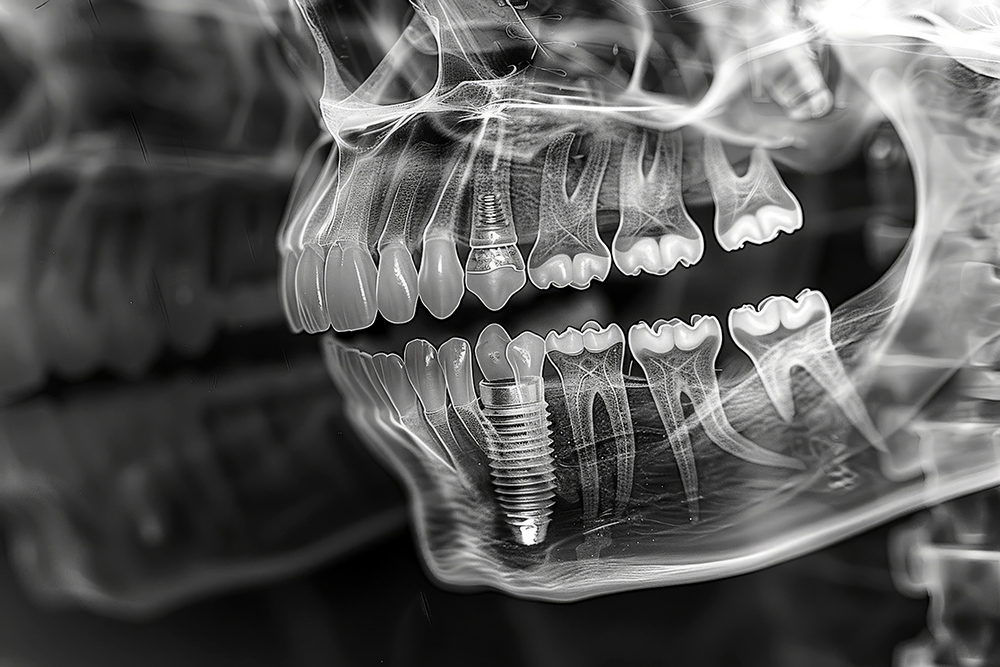

임플란트 시술 전, 의사는 환자와 초기 상담을 진행하며 환자의 요구사항과 건강 상태를 확인합니다. 이때 X-ray 촬영, 3D CT 스캔 등을 통해 환자의 구강 구조를 면밀히 분석합니다. 이 과정을 통해 시술 계획이 구체적으로 잡히며, 필요시 추가적인 치료(예: 뼈이식)가 논의될 수 있습니다.

만약 치조골이 부족한 경우, 뼈이식 수술이 필요할 수 있습니다. 이 과정은 임플란트를 안전하게 고정할 수 있도록 하기 위함이며, 뼈이식 후 회복 기간은 최소 3개월에서 6개월 정도 소요됩니다. 이 시기를 통해 이식된 뼈가 단단히 자리 잡게 됩니다.

본격적인 임플란트 식립 과정에서는 치조골에 인공치아 뿌리(임플란트)를 심습니다. 이 과정은 국소마취를 하며, 수술 시간은 보통 한 개당 30분에서 1시간 정도 걸립니다. 수술이 끝나면 잇몸을 봉합하고, 임플란트가 뼈에 완전히 결합될 때까지 기다려야 합니다.

임플란트가 뼈와 단단히 결합하는 과정을 '골유착'이라고 부릅니다. 이 기간은 약 3개월에서 6개월이 필요하며, 뼈 상태에 따라 다를 수 있습니다. 골유착이 잘 이루어져야만 임플란트가 안정적으로 자리잡고, 정상적인 기능을 수행할 수 있습니다.